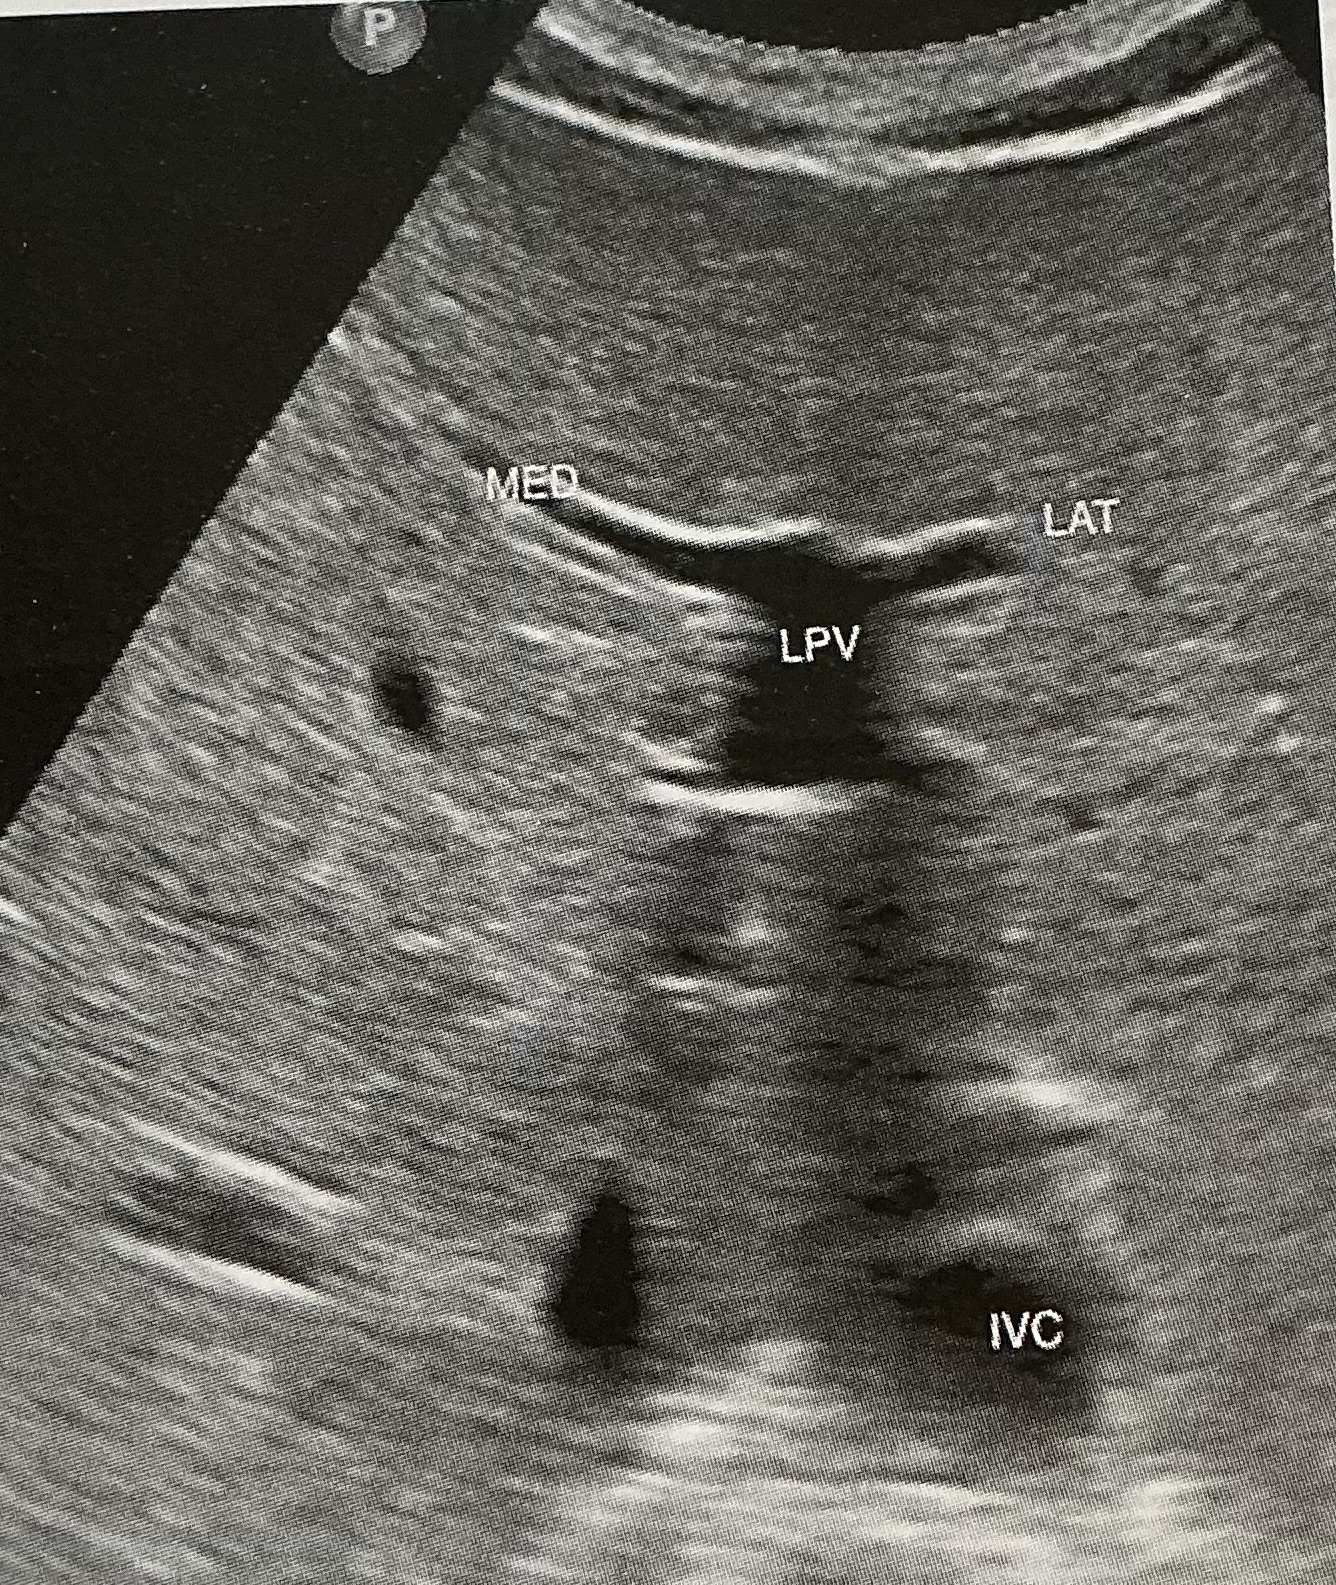

What is the sonographic criteria for differentiating the portal veins and hepatic veins?

origin and drainage; echogenic walls; branching patterns; caliber changes and Doppler signal; segmental locations

Label this picture

what sign is it depicting

Why does this happen?

What sign does the hepatic veins normally depict?

Canadian moose sign

Dilatation from right heart failure

Playboy bunny sign